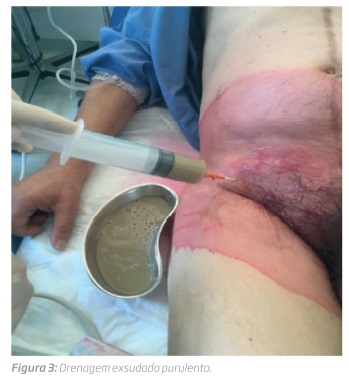

Em Agosto de 2017 esteve internado em Medicina Interna por urosépsis com isolamento em hemoculturas de Escherichia coli multi-resistente tendo tido alta com antibiótico dirigido. Em 5 de Setembro 2017 é observado por tumefação inguinal bilateral e febre. Realizou angio-TC que mostrou infeção protésica, aposição da ansa duodenal D3 com provável fístula aorto-entérica e doença arterial obstrutiva com oclusão das artérias femorais superficiais. Foi feita drenagem de exsudado purulento (figura 3) em grande quantidade e iniciado antibiótico de alto espectro.